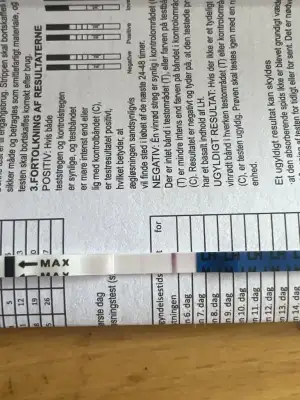

merhaba aranızda hiç ovülasyon veya çatlama gününde göğüslerinde kırmızı çatlak izleri oluşan oldu mu? ben en az 2 kez buna denk geldim ve lh testi ile doğruladım. beyaz çatlak izlerim zaten hep vardı ama ovülasyon gününde kıpkırmızı olup ertesi gün tekrar beyaz oluyorlar. böyle bir şey yaşayan var mı? :)